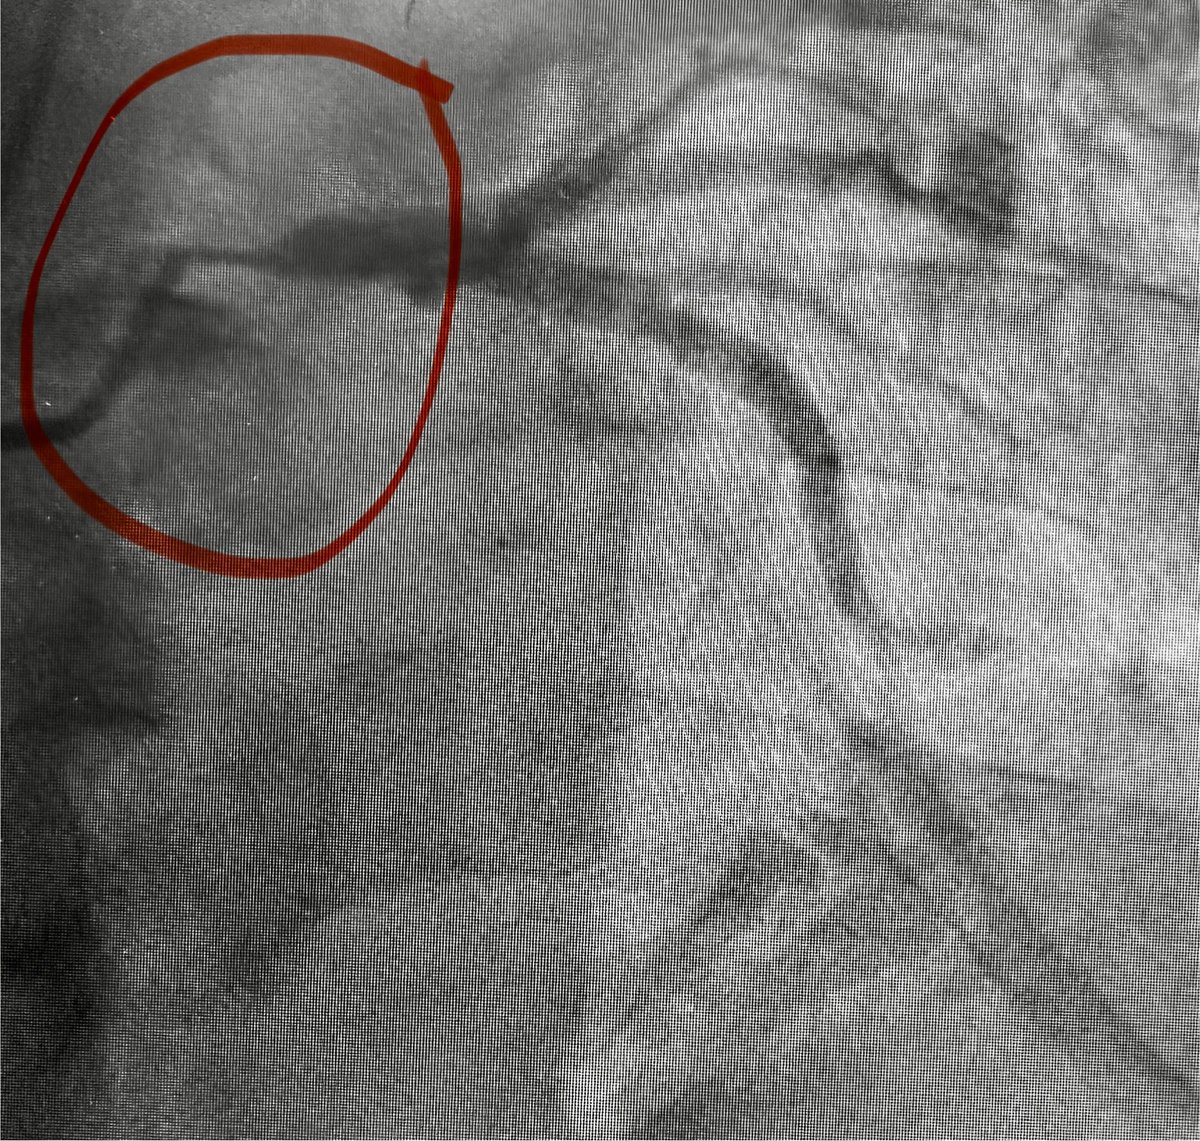

Introducing the percutaneous aorto-coronary bypass graft. The VECTOR procedure revascularizes the left main coronary artery using retrograde and antegrade steps: a retrograde wire exits the left main (distal graft), an electrosurgical wire exits the aortic root (proximal graft), a guidewire rail is created, and a stent graft is delivered from the aorta to the left main. What could possibly go wrong?

ahajournals.org/doi/10.1161/CI…